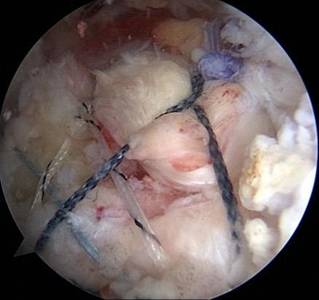

关节镜下肩袖损伤修复术治疗肩袖损伤

优点:损伤小、恢复快。